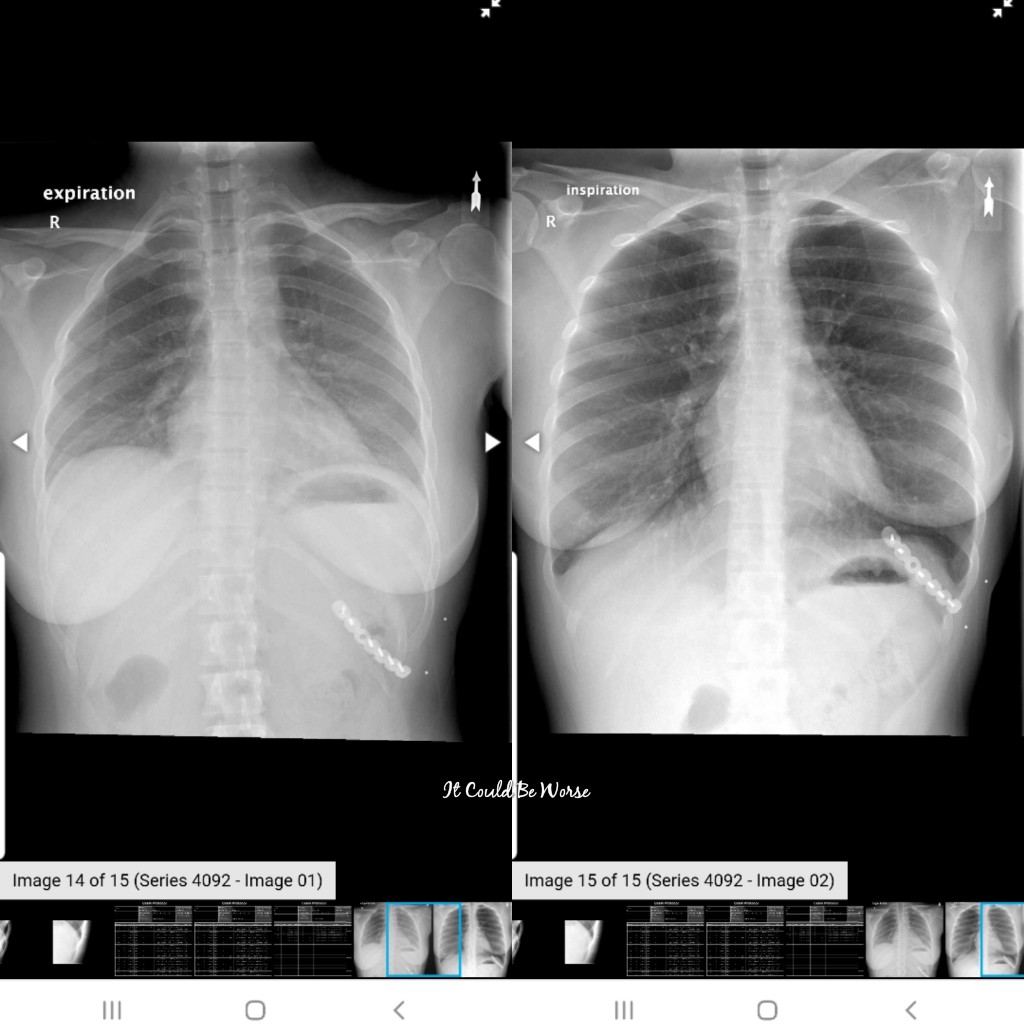

A fluoroscopy, for those of you who don’t know, it is kind of a mix between an x-ray and MRI – to where you can view live images as they happen. I could see the screen and it was me, moving around, looking for a fracture or crack. With the continuous x-ray movement showing, I had to breathe in and out and stretch my body as much as I could without excruciating pain.

So, when we got to the fluoroscopy suite, I got little silver bb markers to place on the areas I had pain. The doctor even noticed that I had placed them on the 10th rib, front and laterally, so what I was saying that was causing pain made sense to him, too.

View X-ray #3 & #4 – You can see the bb’s from the fluoroscopy still on me, too.

We looked and looked for fractures, he thought he possibly saw one but couldn’t confirm it, so yet again I had to leave with no answers. We got a third set of x-rays just to compare, but I had to leave with no information and continue to be in pain.